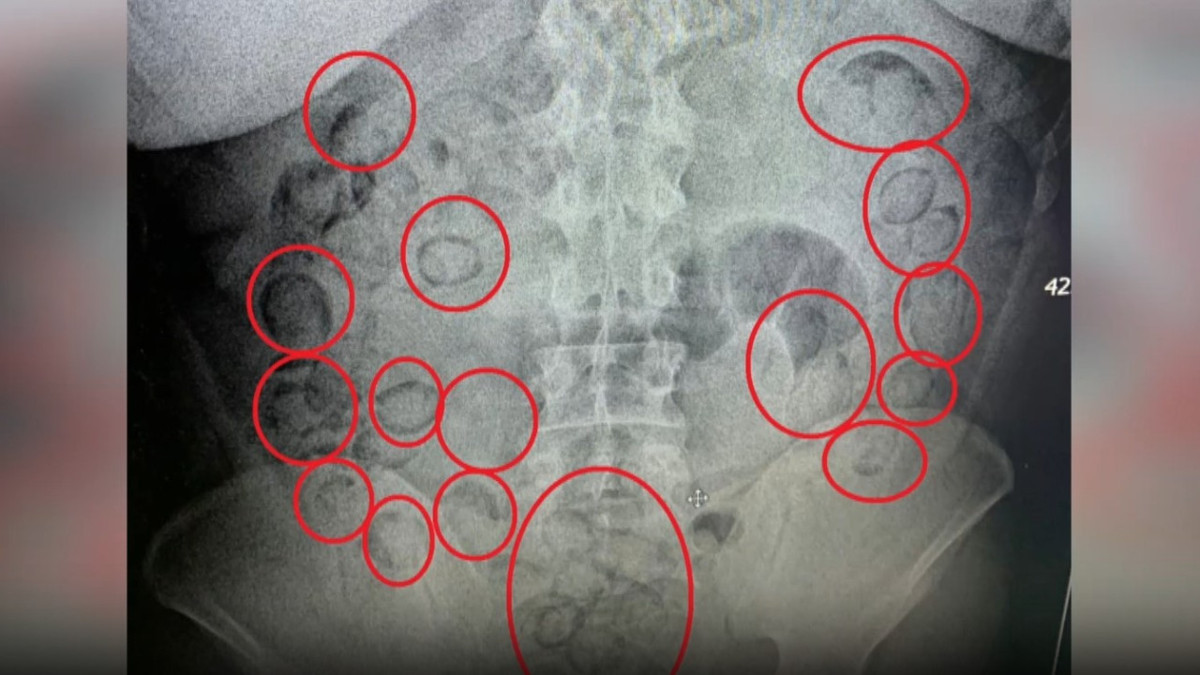

Araçta bulunan A.M. şüpheli davranışları nedeniyle gözaltına aldı. Aksaray Eğitim ve Araştırma Hastanesi’ne götürülen A.M.'nin çekilen röntgeninde midesinde uyuşturucu tespit edildi.

Tıbbi müdahale ile A.M.’nin midesinden 101 parça halinde 433 gram metamfetamin çıkarıldı. Emniyetteki işlemlerinin ardından adliyeye sevk edilen A.M., çıkarıldığı mahkeme tarafından tutuklandı.